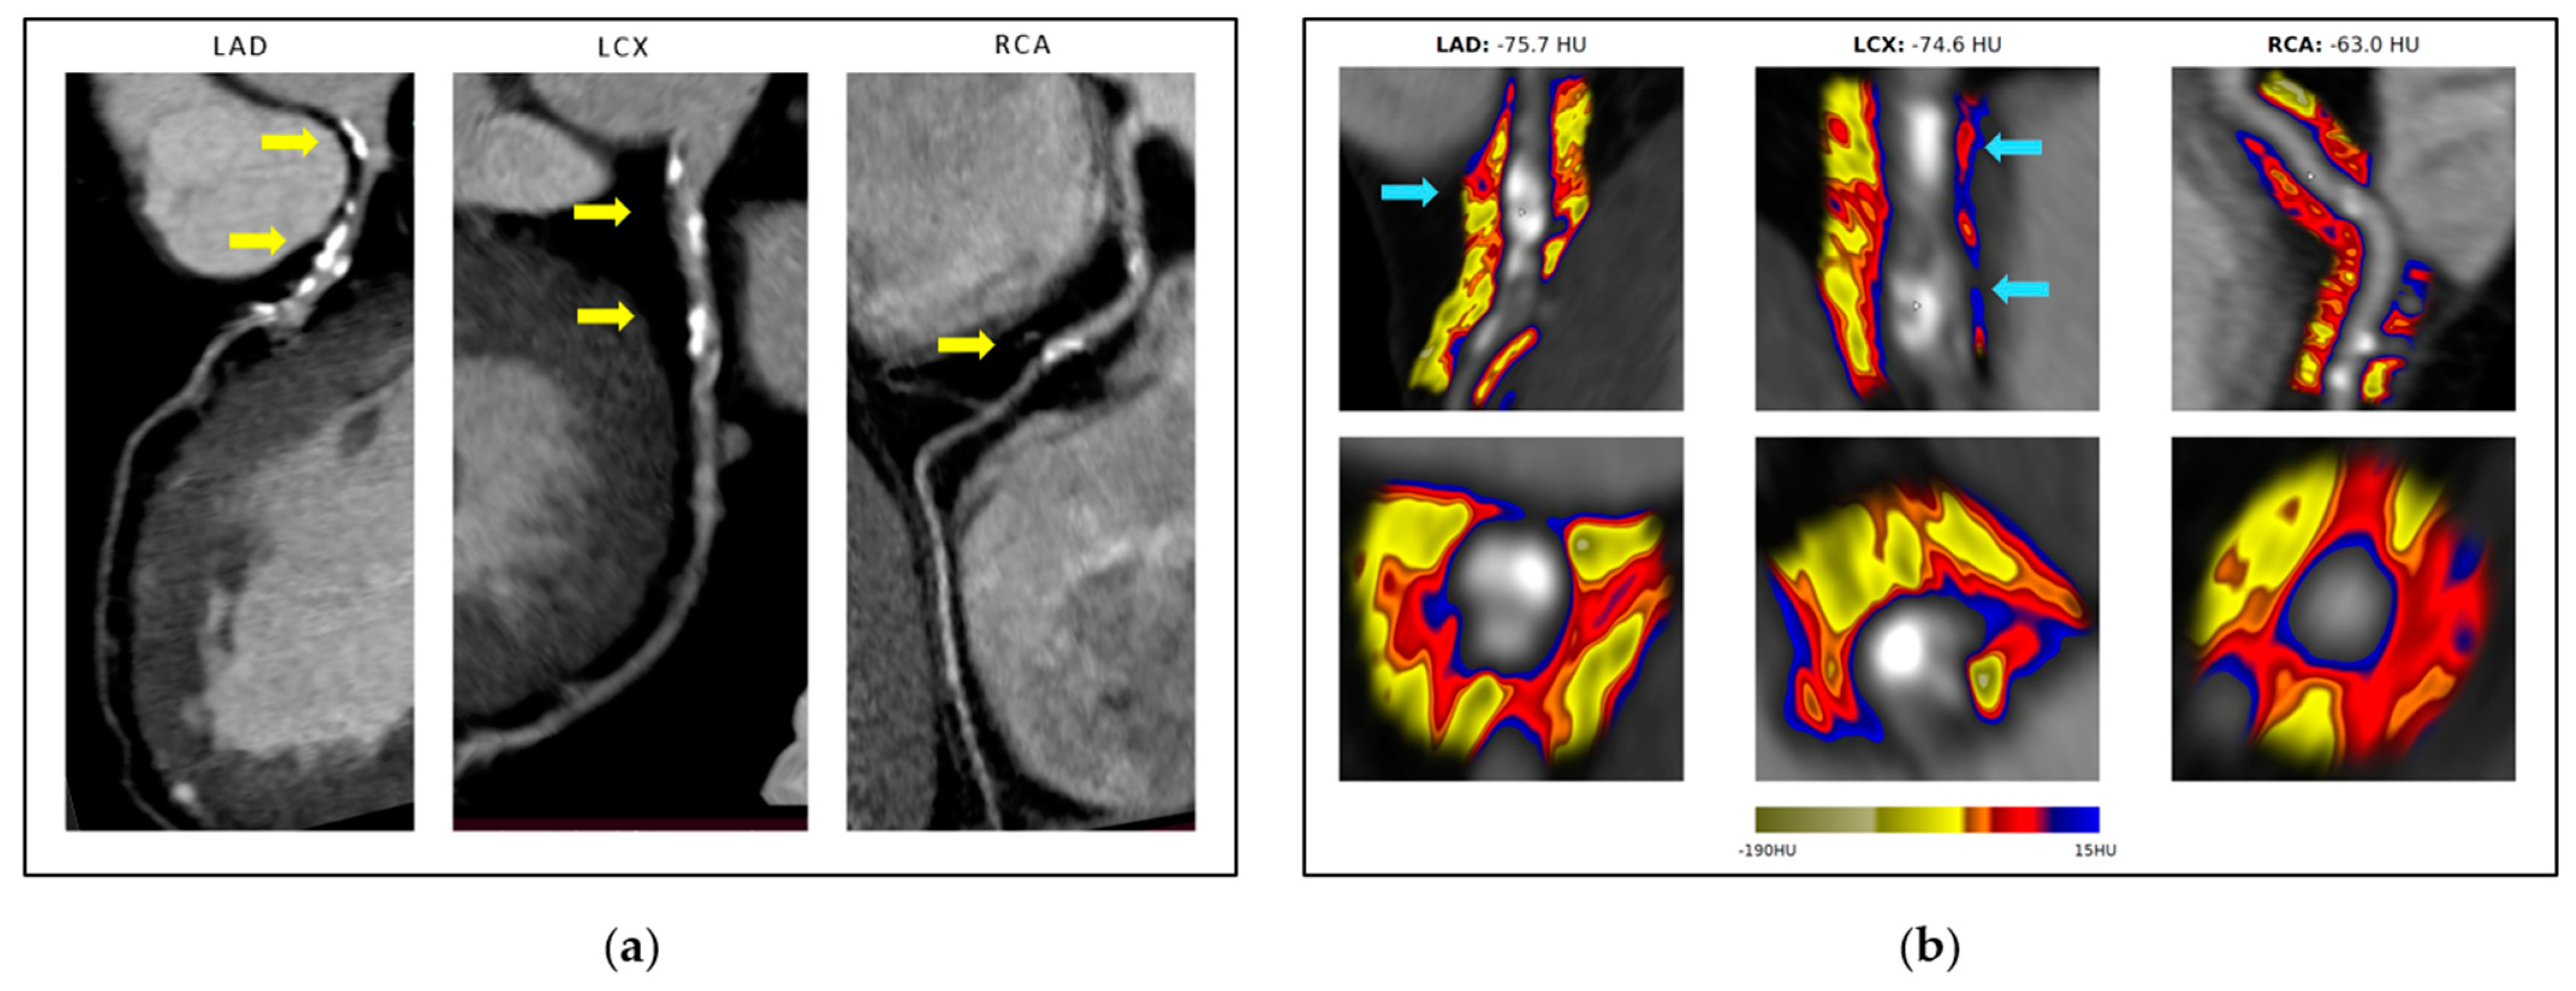

| Fat Attenuation Index (HU) | A non-adjusted, graphic illustration of the level of inflammation in the three primary epicardial coronary arteries. |

| Fat Attenuation Index-Score | A personalized measurement of the quantification of coronary inflammation in the three primary epicardial coronary arteries, adjusted for age and gender, expressed as a relative risk. |